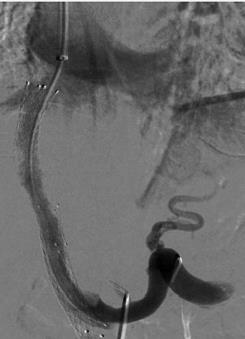

三维路图在经颈静脉门体分流术中的临床应用